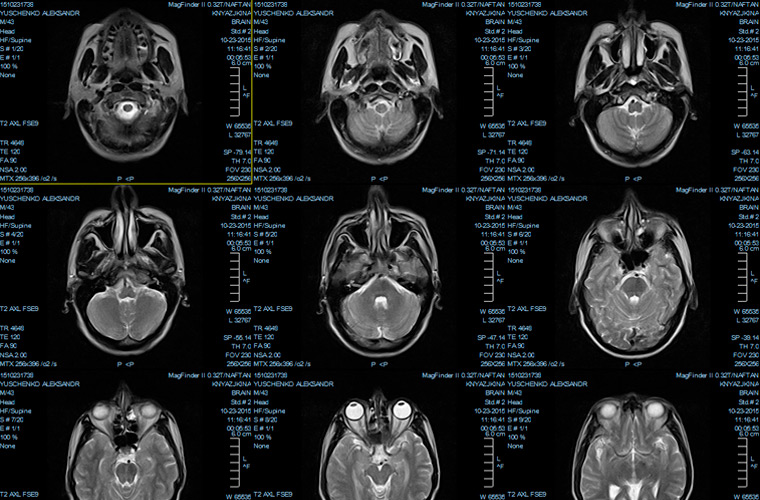

С помощью МРТ получают результаты в виде снимков с обычным и объемным изображением, которые выдаются больному. Результаты обследования записываются на USB-флеш-накопитель.

МРТ проводится рентгенологом. Врач-радиолог поможет расшифровать снимки МРТ, компьютерной томографии, рентгенографии. Специалист описывает результаты не больше 3 суток, поскольку:

- Изучаются документы больного.

- Анализируются результаты исследования.

- Проводится оцифровка рентгеновской пленки в снимок.

- Снимки описываются, делается заключение.

Лечащий доктор объяснит больному результаты обследования. В частной клинике результаты будут расшифрованы к концу дня.